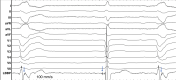

Conduction system pacing (CSP) has emerged as a more physiological alternative to right ventricular pacing and is also being used in selected cases for cardiac resynchronization therapy. His bundle pacing was first introduced over two decades ago and its use has risen over the last five years with the advent of tools which have facilitated implantation. Left bundle branch area pacing is more recent but its adoption is growing fast due to a wider target area and excellent electrical parameters. Nevertheless, as with any intervention, proper technique is a prerequisite for safe and effective delivery of therapy. This document aims to standardize the procedure and to provide a framework for physicians who wish to start CSP implantation, or who wish to improve their technique.